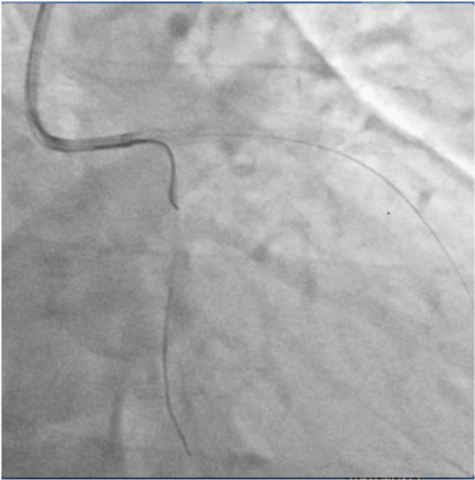

A 7 Fr EBU guiding catheter was employed to engage the LM artery and two BMW 0.014 wires were placed in the distal LAD and LCX arteries. The LM-LAD lesion was pre-dilated with a 2.5X15mm balloon and a 3X18mm zotarolimus eluting stent (ZES) was deployed covering the LM and LAD stenosis (Figure 5). Proximal optimization was done by placing a 3.5X9mm non-compliant (NC) balloon at the bifurcation of the LM artery and inflating it to 10atm (Figure 6). One more BMW wire was negotiated through the distal struts of the LM-LAD stent into the LCX artery (Figure 7), and the jailed wire withdrawn.

Figure 7 Third BMW wire being easily negotiated into LCX artery through struts of LM-Lad stent after proximal optimization.